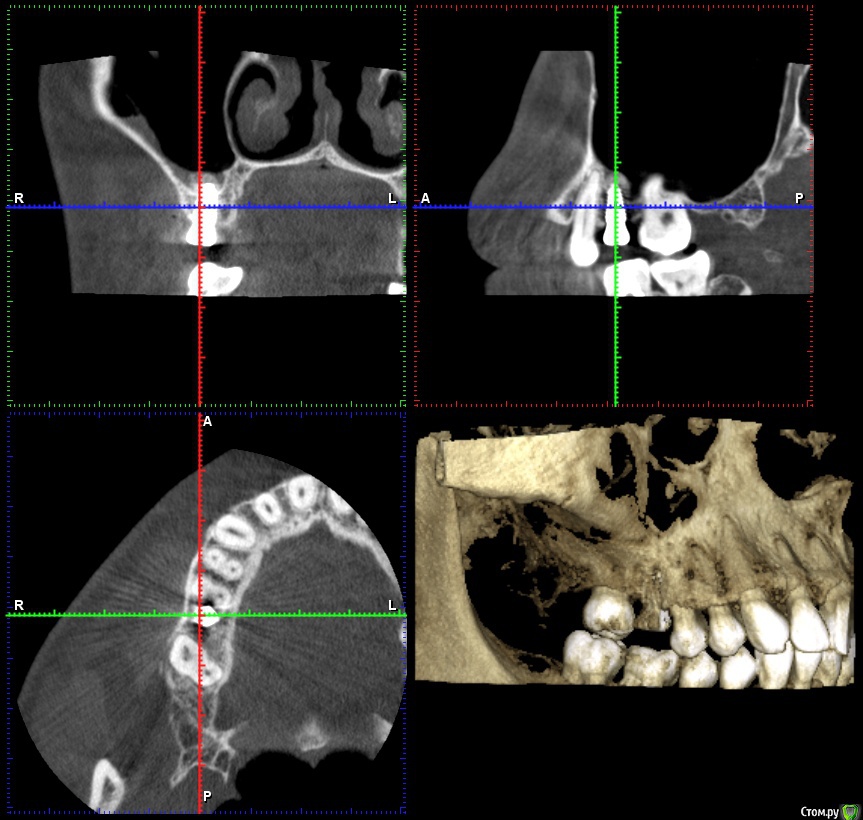

fallnighter Опубликовано 27 августа, 2020 Поделиться Опубликовано 27 августа, 2020 Здравствуйте, уважаемые врачи и иные пользователи форума! Очень прошу вас изучить мой случай и ответить на интересующие вопросы. 01.08.2020 была операция, установлен имплантат AnyRidge на место 6-го зуба сверху, плюс закрытый синус-лифтинг (было только 7 мм. кости), плюс сразу же установка формирователя десны. Неделя после была ужасной, т.к. очень сильно ныли соседний 5 и 4 зуб, сидел на обезболивающих, но в итоге всё благополучно стихло. Для спокойствия также делали прицельный снимок через несколько дней после операции, чтобы убедиться что с этими ноющими зубами всё в порядке (убедились).Прошел почти месяц, болей и дискомфорта нет, разве что волнует меня формирователь десны. Он как будто "вылез" частично, т.е. ранее десна была ниже, даже через неделю после операции, когда от отека уже не осталось и следа, а сейчас поднялась. Прикладываю КТ сегмента до операции и сразу же после. Прицельного снимка, к сожалению, нет (остался в электронном виде в клинике). Также прикладываю фото того, как сейчас выглядит формирователь. Подскажите, пожалуйста, нормально ли он сейчас стоит, есть ли повод для беспокойства? Забивается пища рядом с ним, стараюсь тщательно соблюдать гигиену и пользоваться ирригатором, но очень настораживает что он несколько "оголился" из десны, ведь раньше такого не было. Спасибо огромное всем, кто откликнется! https://yadi.sk/d/EYQJ8w0wxr7EXw Ссылка на комментарий